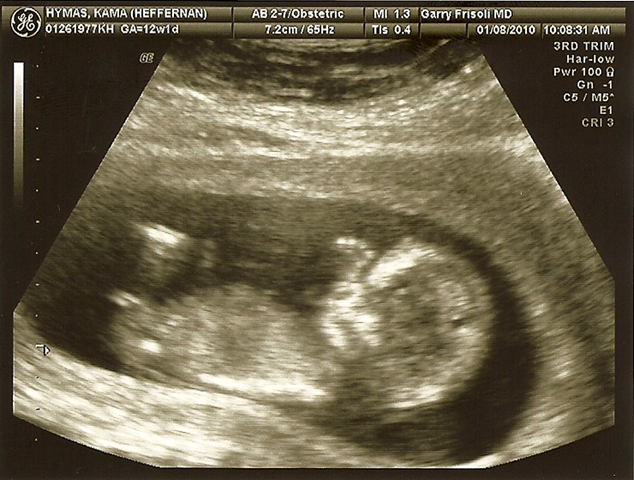

Good News

So there’s our big announcement-Let’s hope it’s a girl! And now I can post one of those cute baby countdowns on my blog! Needless to say this was by far the hardest Christmas of my life. It is NOT FUN to have morning sickness at Christmas time. Let me repeat for anyone who might be considering it. NOT FUN. All I can say is that it is a really good thing I got my Christmas shopping done in November this year or the boys would have gotten Happy Meal toys under the tree. But I will say here that I have the world’s most wonderful husband who picks up all the slack while I take my sick self and lie down. And he never ever complains. He is a saint and I love him very much.